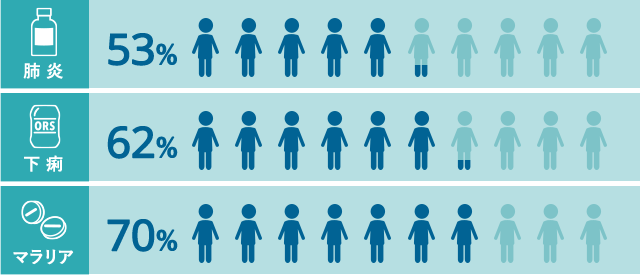

病気になっても適切な治療を受けられない子どもが過半数を占めています。

出典:UNICEF DATA

( Pneumonia 2016, Diarrhoea 2011-2016, Malaria 2013-2015 )